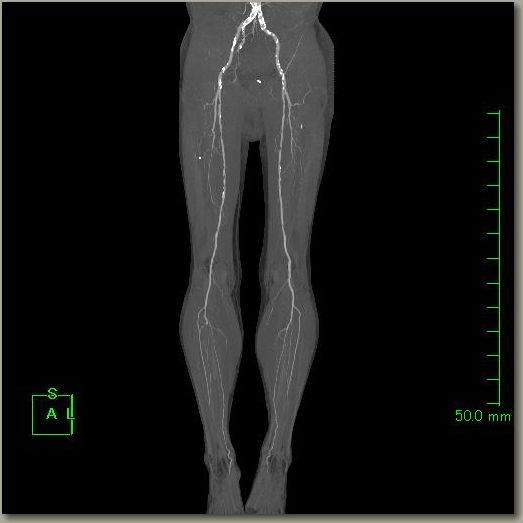

下肢CTA

下肢

下肢の血管